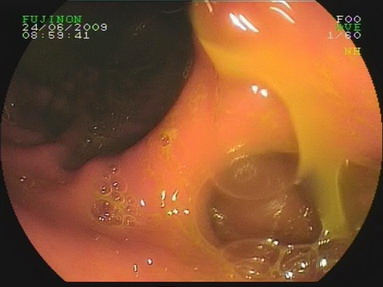

2009.6.24胃镜:

慢性浅表性胃炎,十二指肠淤滞症原因待查,肠系膜上动脉压迫综合症?(胃内可见胆汁样物反流,十二指肠球扩张,降部明显扩张,水平部远端似可见狭窄,持续充气肠腔不能打开。)